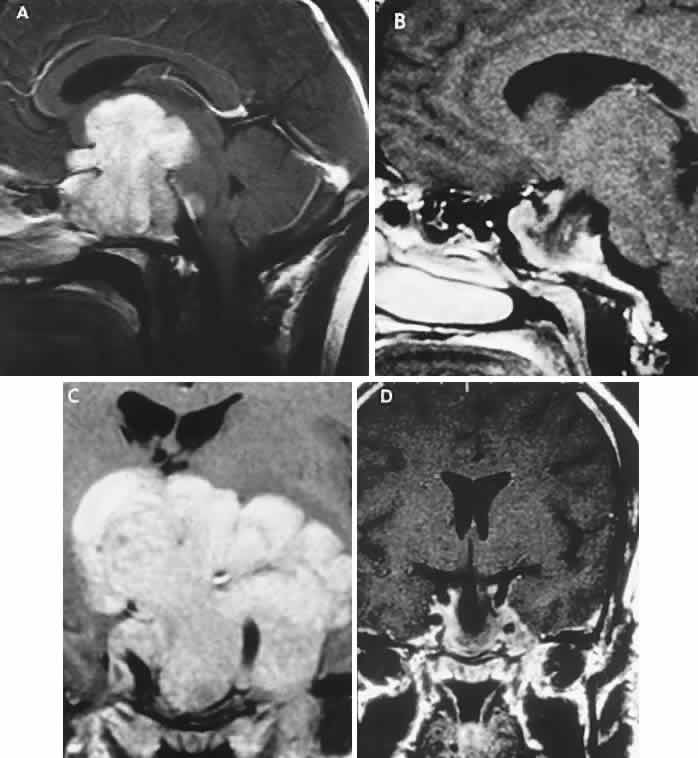

CT scanning retains special relevance to craniopharyngioma diagnosis, currently superior to MRI in detection of calcification and cyst formation (Fig. 7A to C); however, the extent of involvement of adjacent structures, that is, the optic chiasm, third ventricle, and intracavernous carotid artery, is more clearly delineated by MRI (Fig. 7D and E).93 Craniopharyngioma fluid collections are found to be uniformly bright on T2-weighted sequences, but on T1-weighted images, the signal intensity may range from hypointense to hyperintense, reflecting the heterogeneous contents of cysts. Because calcification and cyst formation are hallmarks of craniopharyngiomas, CT is more specific than MRI. At times, intrinsic infiltration of tumor may thicken the chiasm and contiguous optic nerve, a radiologic configuration that mimics glioma.94 Likewise, glioma may be simulated when the optic canal is invaded and enlarged, but accompanying bony erosion of the sella weighs heavily toward craniopharyngioma.

Fig. 7. Computed tomography scan of a large, multicystic craniopharyngioma. A. Axial section through the sella shows destruction of the bony skull base. Axial (B) and coronal (C) sections show cysts (white arrows) and calcification (arrowheads). Contrast-enhanced magnetic resonance imaging of the craniopharyngioma. Sagittal (D) and coronal (E) sections with gadolinium show solid and cystic (arrows) portions.